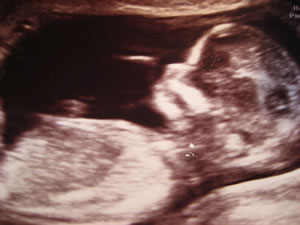

In't Mudderliev. Bild © Elene Scholz, Anke Nissen

Ultraschall. Bild: Guimi/Wikimedia Commons

Un enes Dags bringt se denn ok all en Bild vun di mit na Huus. Se hebben mit so'n Schallapperaat ehr den Buuk beföhlt. De Appraat föhlt ok in den Buuk rin, wo du swäven deist. Un dat lichten se denn af to en Foto.

Wo de warden Mudder sik freut! Un de warden Vadder natüürlich ok. Se dregen mit dat Bild rüm; jeder kriggt dat enen Dag. Se wiesen dat Foto mit groote Freud all ehre Fründinnen un Frünnen, wißlich ok de Grootöllern.